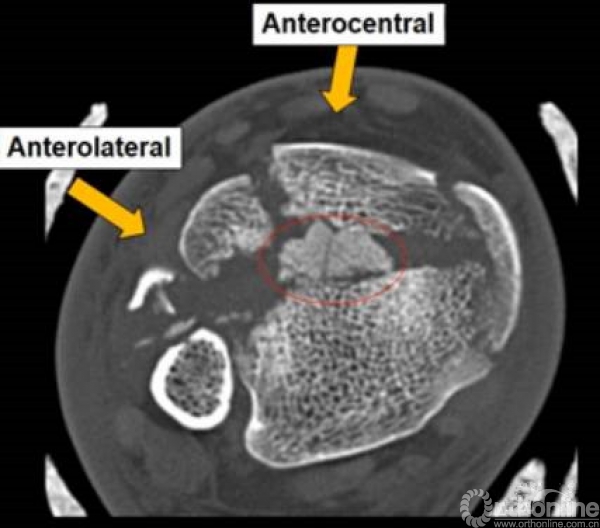

cole在2013年jot发表的文章描述了pilon骨折的骨折线图根据多例病例汇总到一起,颜色越深则越骨折线经过的可能性越大。

他将pilon骨折大致的骨块进行了分类,分别为后、前内、前外三个骨折块。